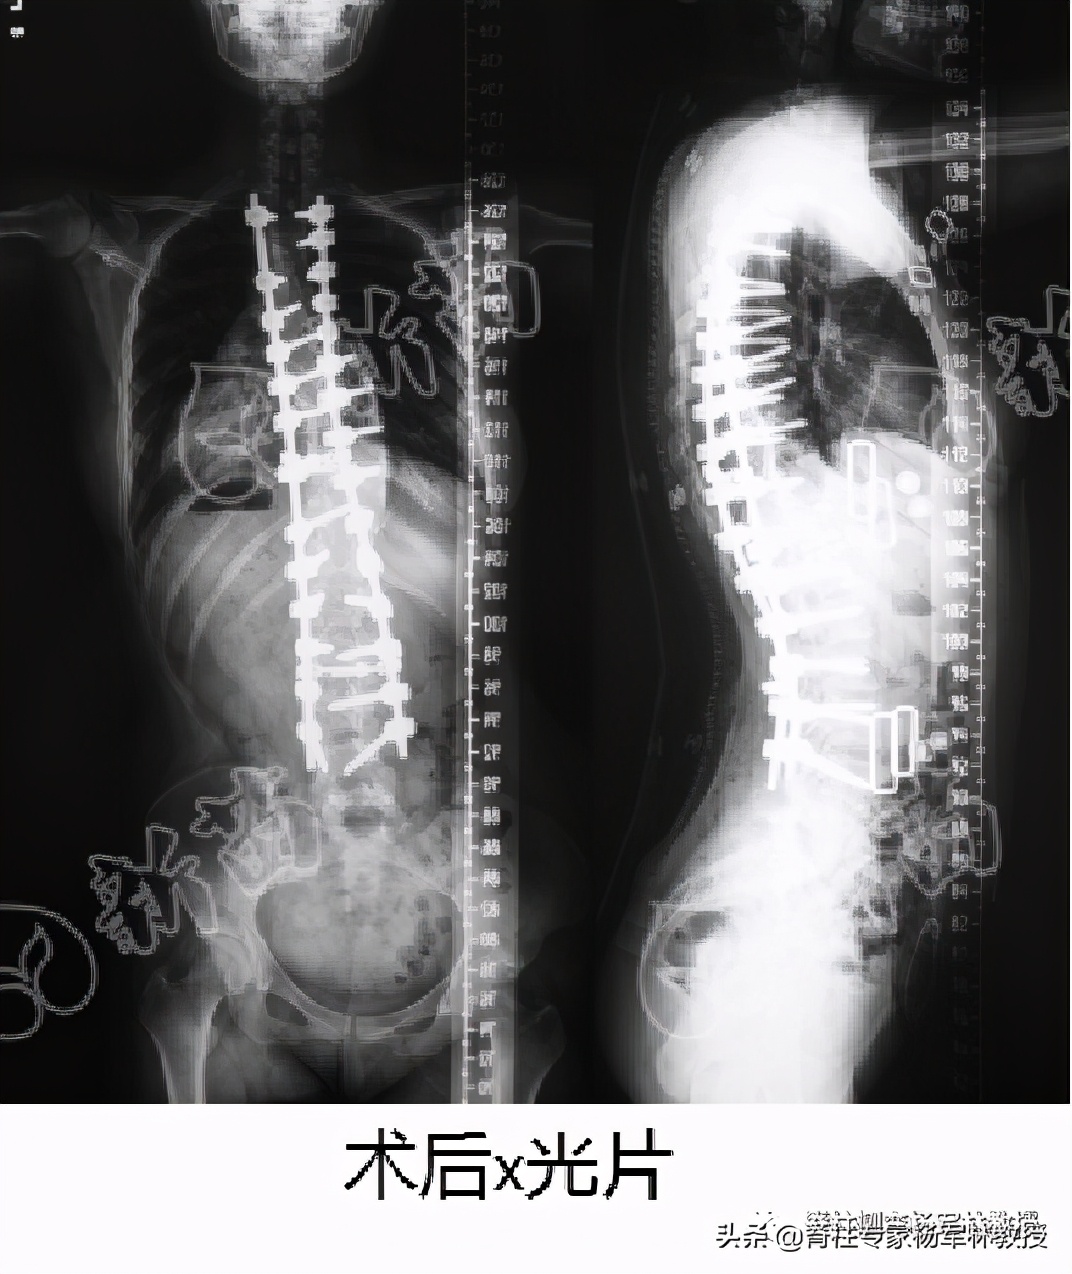

3岁时,家人就发现我脊柱不太正常。直到青春期开始发育的时候,脊柱侧弯加重,从那以后就没有长高,一直停留在141公分,但是手术后长高了6公分。很开心。

一两个月后,侧弯只减轻了几度,练到4个月时,已经完全没效果了,但是钱却花了六七万。当时我已21岁,侧弯有80多度,骨头很硬,也害怕把脊柱压断。本来家人就不支持我去北京,看不到治好的希望,我戴着支具回家了,在网上买了一台牵引机在家锻炼。

经过一段时间的了解,我发现当时中山医院的脊柱侧弯手术技术,在全国乃至全世界都很厉害,有很多比我严重的都治好了,那我的肯定没问题。当时我住院期间,亲眼看到两个在外面没做好,在中山医院杨军林教授给做的翻修手术。

手术后,在医院附近租了个小屋休养,我让爸爸每天炖排骨汤给我喝。开始身体比较虚弱,二十多天后回家,可能家里吃的东西比较天然,都是土鸡土猪,营养跟上了。后来回学校,我能拿的行李竟然比术前还要多。

作为一个天生的乐观派,术后我变得更加自信,从黑、土、矮、驼变得又白又瘦又直,而且还很好看,起码比之前好看太多了。同事都问我是不是悄悄整过容?